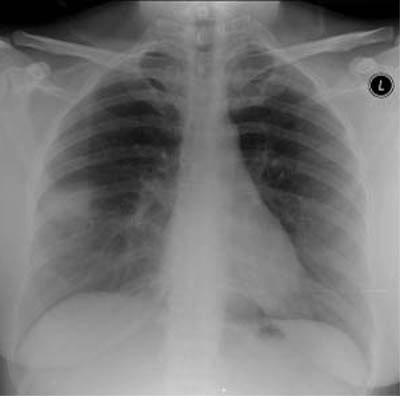

| Radiological signs of SARS include presentation with focal airspace opacity, seen here in the periphery of the right midzone (top image), in approximately 46% of the cases. In 29% of the cases with abnormal radiographs, there were bilateral multifocal opacities (middle image) as well as diffuse opacities, seen here principally in the right lung (bottom image). Images courtesy and copyright of Dr. Narinder Paul, Princess Margaret Hospital, Toronto, ON |

Approximately 25% of the patients are showing normal chest x-rays on admission for SARS, according to Paul. The remaining 75% of patients with abnormal chest x-rays can be divided into two groups.

About 46% of the patients are showing unilateral focal opacities; the remaining 29% are presenting with bilateral multifocal opacities or diffuse opacities. Of these signs, the most worrisome are the diffuse opacities, Paul said, because these patients have shown the highest rate of mortality. Conversations with physicians in SARS-affected areas of China have revealed that these percentages are roughly the same in China, he said.